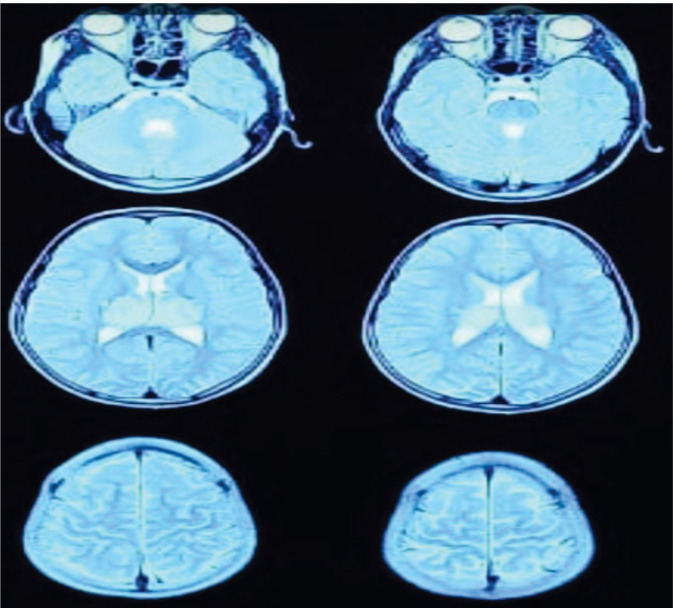

New daily data on the COVID-19 pandemic are circulating globally. This disease usually appears with respiratory symptoms such as cough, shortness of breath, and fever. The neurological complications of the disease are somewhat known in adults but rarely reported in children. Acute necrotizing encephalopathy of childhood (ANEC) is one of the brain complications associated‌ with Coronavirus disease that usually has a poor prognosis in children. In this case, we report a rare case of a 7-year-old boy who was referred to the hospital with symptoms of convulsions after contracting COVID-19 and developed cerebral necrotizing encephalopathy caused by COVID-19 infection. Although ANEC is a rare disease, clinical examination and MRI and CT scan findings play an essentialrole in diagnosing and treating the disease.‌.

Abstract Image